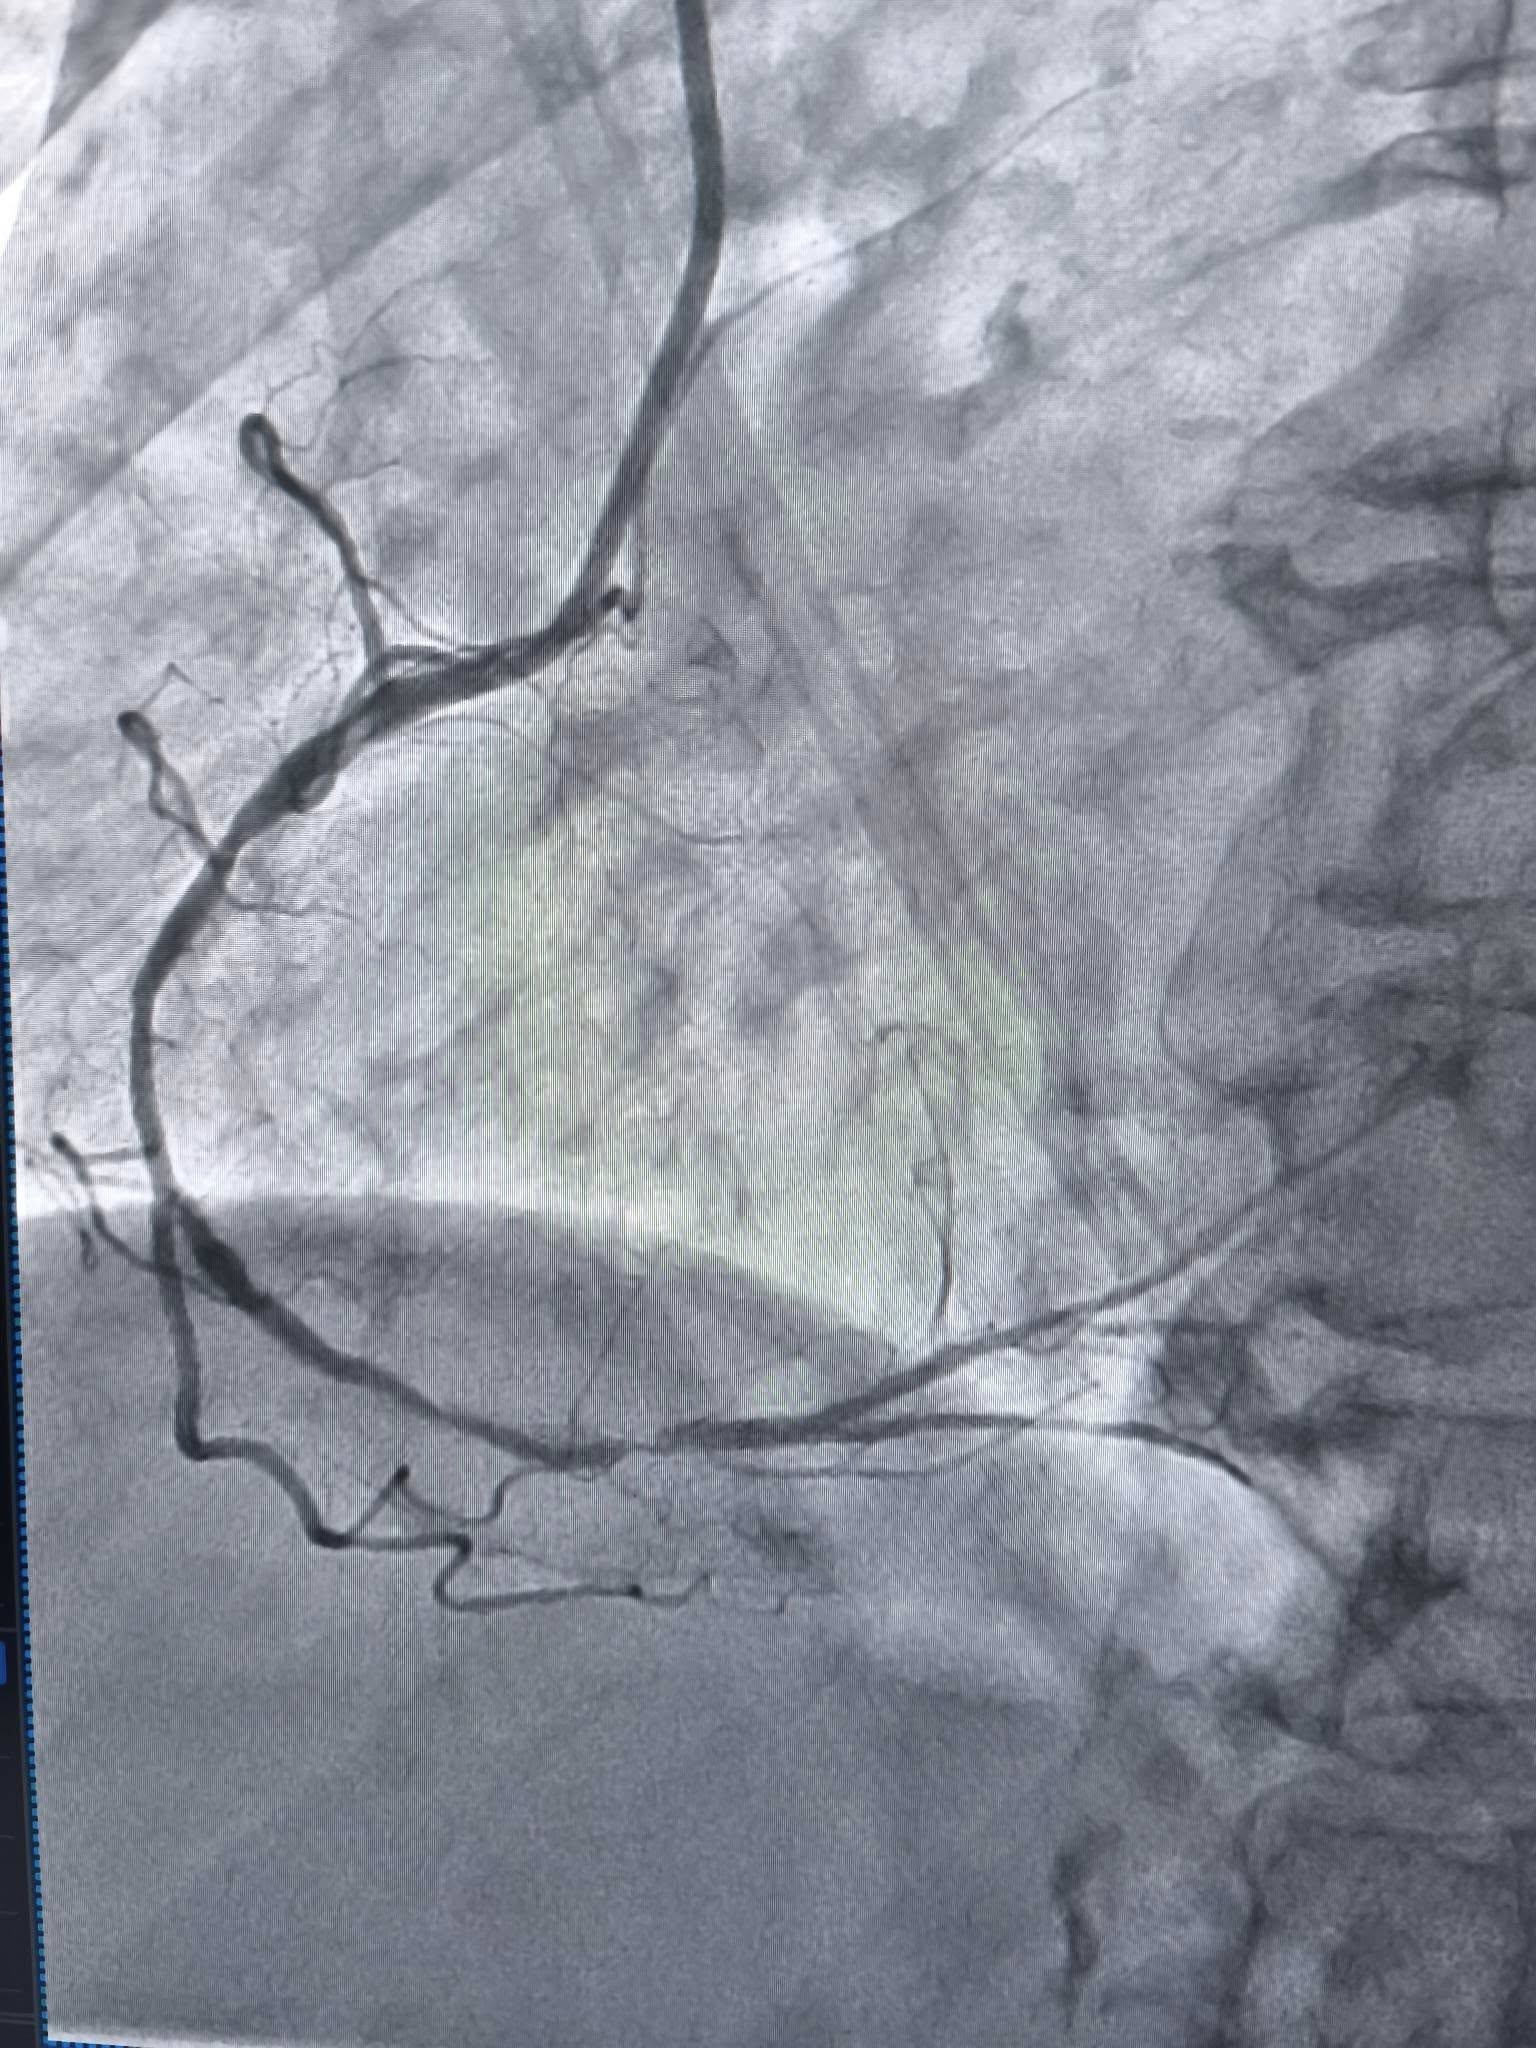

У таких ситуаціях на допомогу приходить ротаблятор – спеціальний пристрій із буром, покритим діамантовим напиленням. Він дозволяє «модифікувати» кальциновану атеросклеротичну бляшку, фактично шліфуючи її та відновлюючи можливість для подальшого стентування судини. Саме таким методом лікарям вдалося ліквідувати перешкоду в артерії та успішно імплантувати стенти.

«Це втручання стало важливим кроком для нашої лікарні та всієї області. Ротаційна атеректомія застосовується у найскладніших випадках кальцинованих уражень коронарних артерій, коли стандартна ангіопластика неефективна. Виконання такої процедури означає, що пацієнти Тернопільщини можуть отримати сучасну високоспеціалізовану допомогу без необхідності їхати в інші регіони», – наголосив Богдан Маслій.